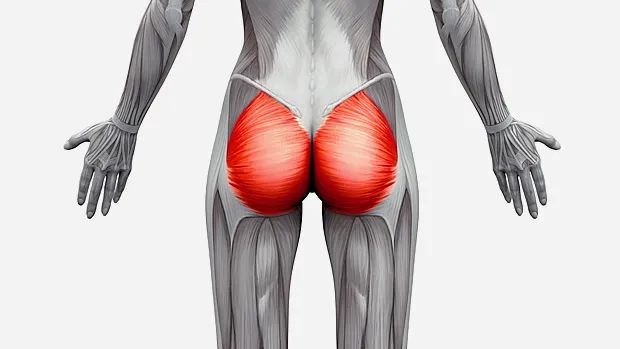

·原因: 疼痛大约在屁股摺痕处。尤其是在你膝盖伸直且将身体向前弯腰时,症状会更明显。这种型态的疼痛表示是连接到骨盆的腘绳肌肌腱受伤,这通常是因为过度的拉扯腘绳肌。(如在瑜伽中:当瑜伽练习者需要保持双腿笔直向前弯曲,然后强迫自己摆姿势时,可能最终会损伤肌腱。)当我们的肌腱受伤,腘绳肌会自然的收缩,试图去保护受伤的肌腱。然而我们认为的是:"腘绳肌紧绷又疼痛,要去伸展它,疼痛自然会消失了",而这样的方式却无法让肌腱修复,反而是重复使其受伤——过度伸展然后再受伤,这样的循环会使复原时间变更长。较好的方式是借由适当地收缩腘绳肌来增加受伤区域的循环,如果可以的话,做简单轻微的伸展。当疼痛急性期结束后,你可以慢慢增加伸展的角度。您的朋友或患者中,是否有人向你这样抱怨过:我的髋部在走路、睡觉时会痛,物理治疗师建议他作核心运动,骨科医师诊断他是梨状肌症候群,也试过请按摩师放松他紧绷的髂胫束。经过仔细的检查后,确认了他疼痛的位置,疼痛的症状都指向无力的外展肌群,造成骨盆位置不良,导致某些肌肉群去代偿。当开始训练他的外展肌群,很快地他的疼痛就不见了。此型态的疼痛通常会出现在臀部外侧或上侧,可能会向下至大腿的外侧。它通常是在散步跟晚上侧躺在患侧时更糟。薄弱的外展肌群,紧绷的髂胫束可能是引起疼痛的一种因素。这种疼痛常被认为是髂胫束的问题,所以借由伸展髂胫束,或用滚筒去放松,这会非常有效,但并没有解决问题的根源-外展肌无力,除非你去加强肌力,否则问题会一再出现。你需要锻炼你的髋外展肌,可以利用单脚站,另一侧大腿对抗重力做髋外展动作,两侧轮流施行,让髋外展肌做为稳定以及动作的功能角色。大家知道坐骨神经分布的范围到底有多大吗?它是你的身体里最长的一条神经,从下段脊椎一路延伸到脚,而且它也非常的粗,大概就像是你的小指头一样粗,穿过你的脊椎与髋关节。因为这条神经粗又长,它可能在很多地方被挤压到,而造成类似坐骨神经痛的症状。两个常见被挤压位置在下背部(腰椎椎体间)跟紧绷的梨状肌下面。梨状肌是一条很小的肌肉,当它太紧绷时可能会造成很多困扰。它位于髋部深处,在髋关节弯曲状态下,负责带动髋关节外转跟外展。紧绷的梨状肌会造成屁股痛,但当它压迫到通过梨状肌下面的坐骨神经时,就会使情况变得更糟。疼痛通常会出现在臀部中间的位置、下背部,或任何坐骨神经通过的地方。症状也有可能是脚麻或无力。如果是因为椎间盘突出引起的坐骨神经痛,是比较大的问题,超过我们本篇所要介绍的范围,在物理治疗师的指导下,加强核心肌群的运动是个不错的方式。如果疼痛是因为紧绷的梨状肌,我们可以着手于放松紧绷的肌肉。·较好的方式:利用我们常见的”收缩-放松-伸展原则”(Contract-Relax-Stretch principle)步骤①:从收缩周围肌肉开始(尤其是臀大肌),来增加此区域的血液循环。步骤②:然后我们可以轻轻的收缩梨状肌 (contract the piriformis ),让它慢慢放松掉原本慢性的收缩(如果不会感到疼痛),搭配温和的伸展。我们可以借鉴瑜伽中的动作,像是勇者式二(Virabhadrasana 2)、侧三角伸展式(Utthita Parsvakonasana)跟蚌蛤式都可以让梨状肌收缩,而在站姿下利用椅子做扭转动作,以及半鱼王式(Ardha Matsyendrasana)是伸展梨状肌最好的选择,因为此姿势会让你的脚处于弯曲、内收,但不会外转的姿势,这对于梨状肌是比较温和的姿势。步骤③:当你觉得你已经准备好在伸展加入外转的动作时,你可以选择穿针引线式(Thread-the-needle pose)来取代鸽式(Pigeon)或牛面式(Gomukasana),这会让使梨状肌受到较小的力矩。当你练习这些动作后,你就可以试着做鸽式(Pigeon)或牛面式(Gomukasana)。PS:但有些学生即使练习很久也还是没办法完成鸽式或牛面式。此外,由于过紧的内收肌群会使髋关节呈现内转姿势,使梨状肌产生额外的压力进而压迫到神经,所以也可使用相同的方式来舒缓内收肌群的慢性紧缩。紧绷的腘绳肌也会造成坐骨神经受压迫,所以对于缓解此肌群的张力也是很有效果的。请记住,即使最简易的腘绳肌伸展运动也可能造成一位有坐骨神经痛症状的人极大地疼痛,所以建议用前面提及到第一种臀部疼痛的腘绳肌伸展原则。 请记住,一个疼痛症状,有可能是许多原因造成的。如果您的疼痛在你经过一番努力后,仍然存在,应该是要去寻求专业建议的时候了。